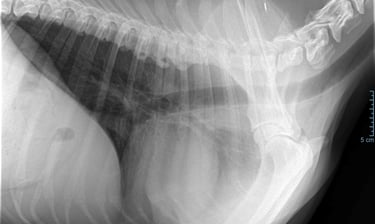

Hartonderzoek - Echocardiografie - Electrocardiografie (EKG) - Radiografie

Radiografie (RX)

Een RX is geschikt om botbreuken, een longontsteking, de hartgrootte, arthrose,....op te sporen.

Als de hond - kat niet lang genoeg stil kan blijven liggen dan is een verdoving noodzakelijk. Voor RX van het heupgewricht is een volledige verdoving noodzakelijk.